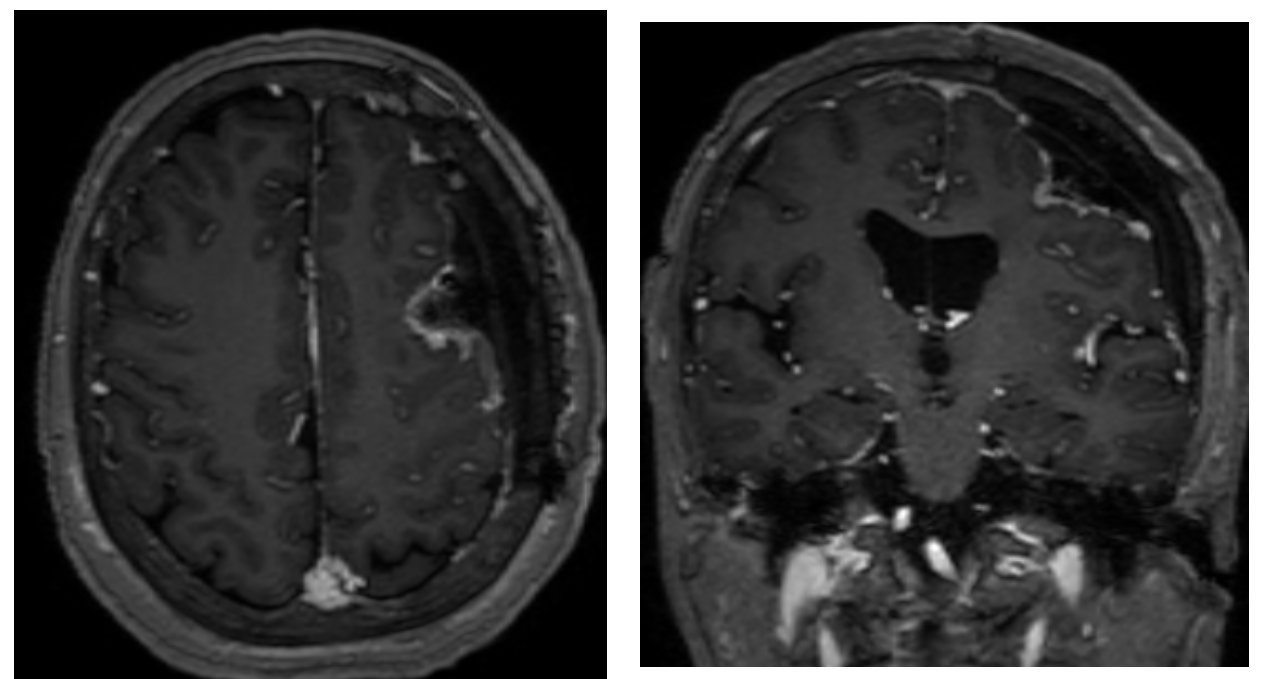

术后MRI